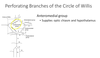

An issue with which artery / vein would cause issues with:

• optic chiasm and hypothalamus

Perforating Branches of the Circle of Willis:

Anteromedial group

An issue with which artery / vein would cause issues with:

- lenticulostriate

- anterior perforated substance

- interior of hemisphere (basal ganglia)

Perforating Branches of the Circle of Willis:

Anterolateral group

An issue with which artery / vein would cause issues with:

- crus cerebri, middle/caudal hypothalamus, and thalamus

- posterior perforated substance

Perforating Branches of the Circle of Willis:

Posteromedial group

An issue with which artery / vein would cause issues with:

• thalamus and choroid plexus of lateral and third ventricles

Perforating Branches of the Circle of Willis:

Posterolateral group